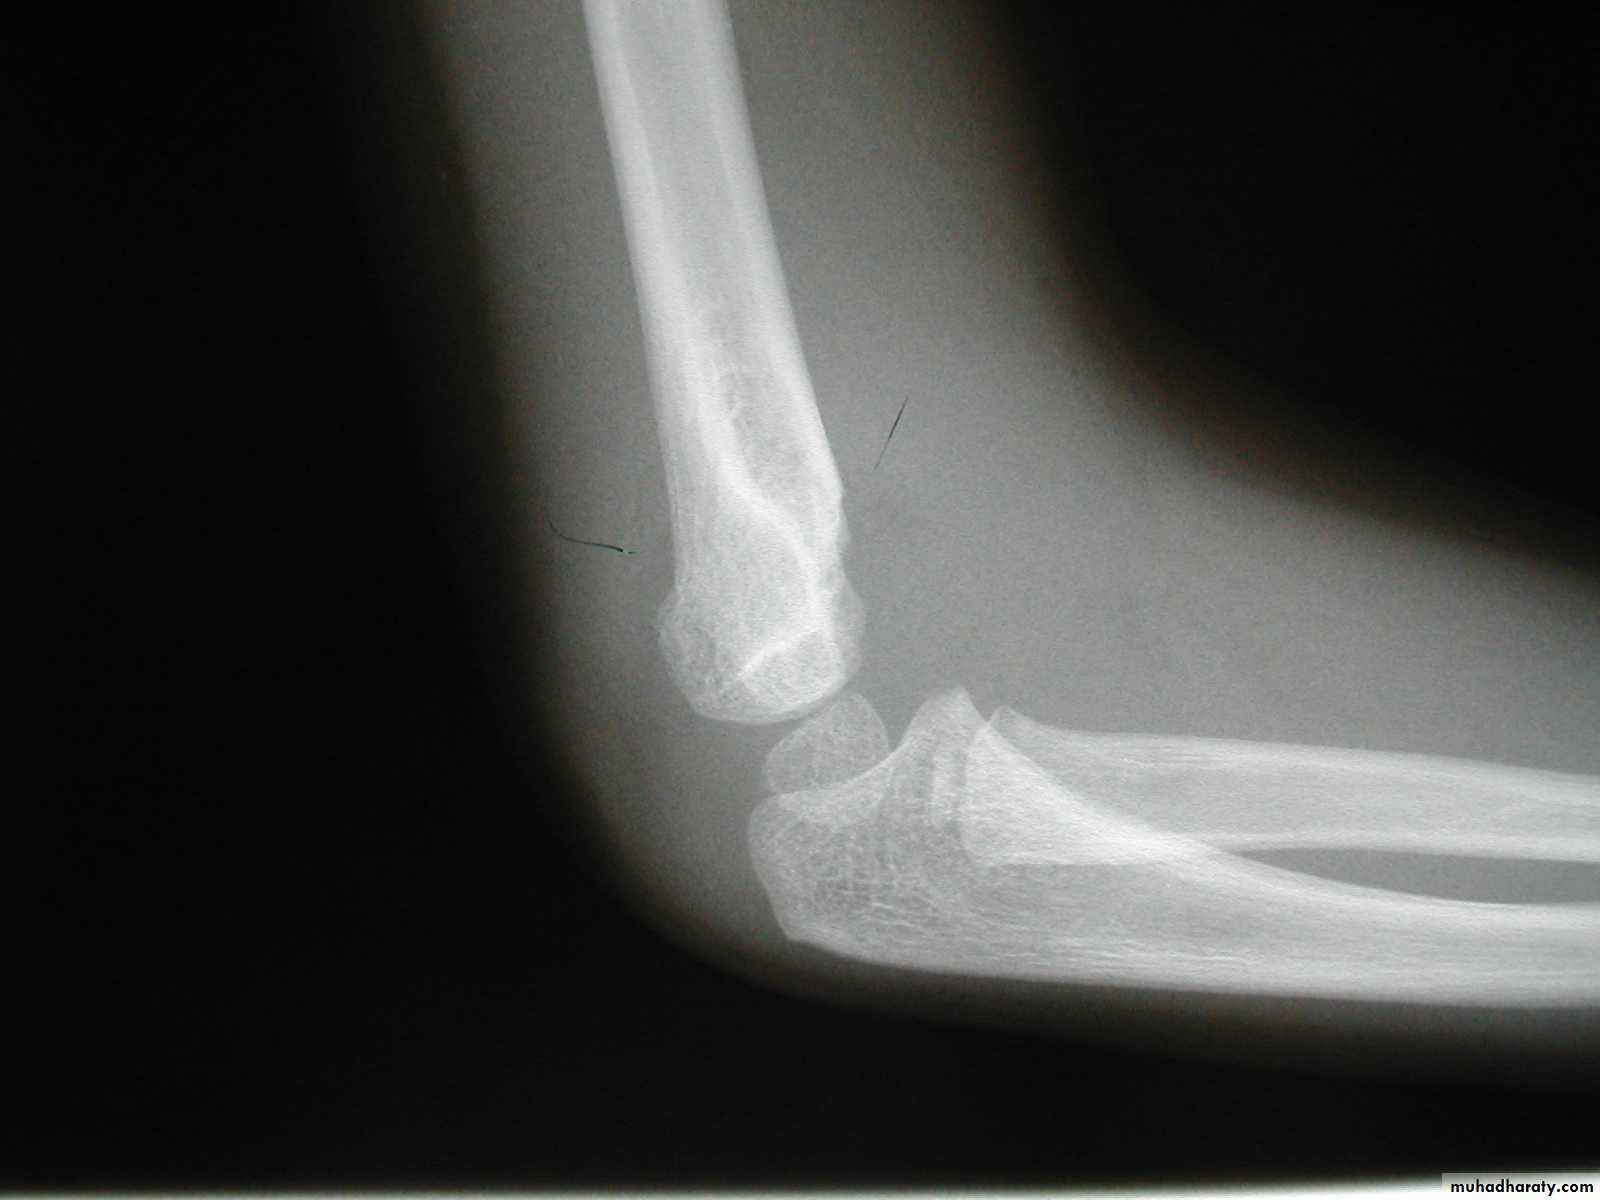

Injury film

3 wks post fracture

fat pads displaced

Type I suspectedPeriosteal new bone

The original suspicions of

a fracture are now confirmed.